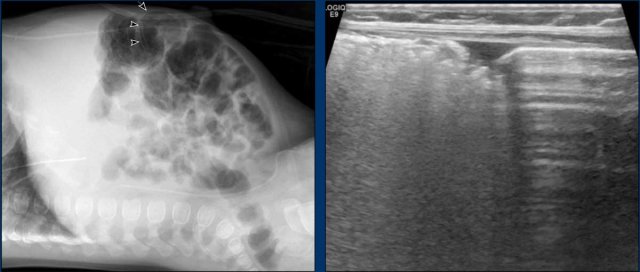

Images

4-month-old

boy operated for complex cardiac disease, now with bloody stools.

Abdominal

x-ray demonstrates pneumatosis in bowel wall (arrow).

This is also seen on

ultrasound in the bowel to the left, whilst the healthy bowel to the right

shows normal air reverberations.